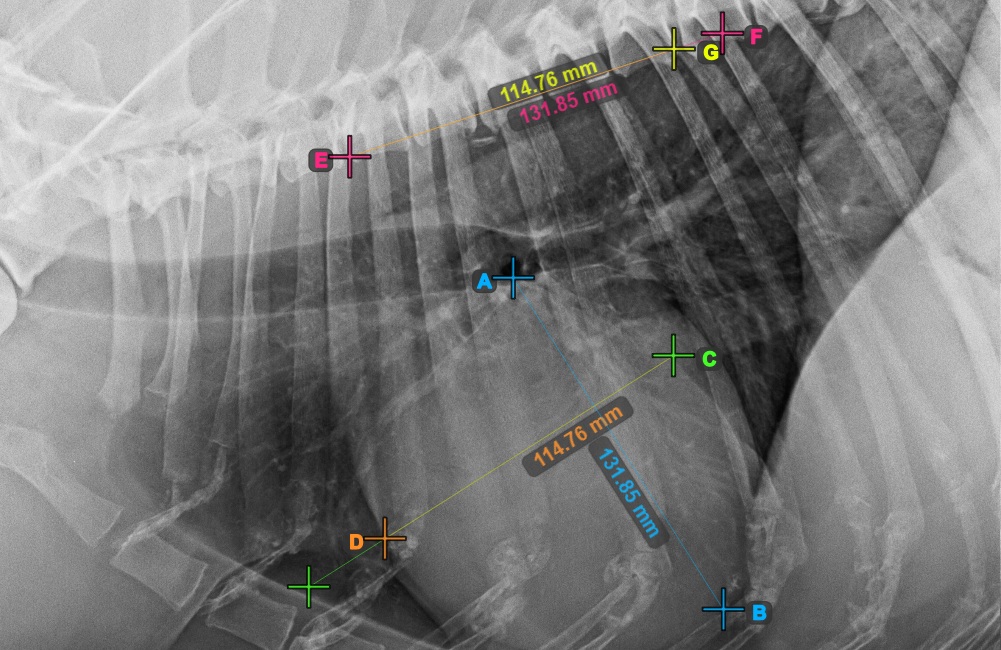

Start the measurement by marking the Bifurcatio tracheae, near the top of the heart.

The image below represents a typical placement of the Bifurcatio tracheae point.

Complete the long axis of the heart by marking the Apex point, near the bottom of the heart.

The image below represents a typical placement of the Apex point.

Continue the measurement by marking the widest right (cranial) point of the short axis of the heart.

The image below represents a typical placement of the most cranial point on the short axis of the heart.

Complete the short axis of the heart by marking the widest left (caudal) point.

The image below represents the typical placement of the most caudal point on the short axis of the heart.

Identify the beginning of the T4 vertebra (the fourth vertebral body of the spine), counting from the initial point of the spine. Mark the beginning of the T4 vertebrae to continue the measurement. The software will draw lines from the marked point along the spine. The length of the lines depends on the measured long and short axes of the heart.

The image below represents the typical placement of the point at the beginning of the fourth vertebral body of the spine.